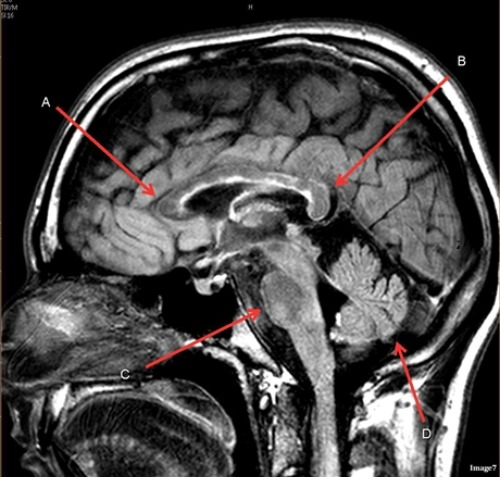

Letter D in Image 7 is pointing to:

B. Cerebellum

Letter A in Image 7 is pointing to:

D. Genu of the corpus callosum

Letter B in Image 7 is pointing to:

E. Splenium of the corpus callosum

Letter C in Image 7 is pointing to:

A. Pons

Image 7 is an example of a _____ weighted sequence acquired in the ______ scan plane.

B. T2 FLAIR; Sagittal